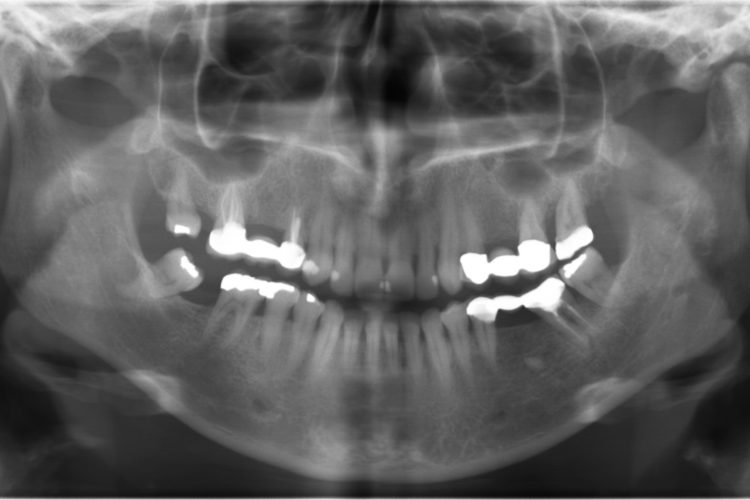

Dental Diagnostic Imaging Center Affordable Radiographs, 3D Dental Diagnostic Imaging Center Blue Springs Mo Saint luke’s offers convenient outpatient imaging at four locations in the kansas city metro. The radiology department at st. Mary’s medical center offers some of the most advanced diagnostic radiology equipment in the eastern jackson county. Learn more about outpatient diagnostic imaging centers. Mary’s heart center’s team of specialists employ a full range of tests to make an accurate diagnosis. Diagnostic Imaging Center Blue Springs Mo.